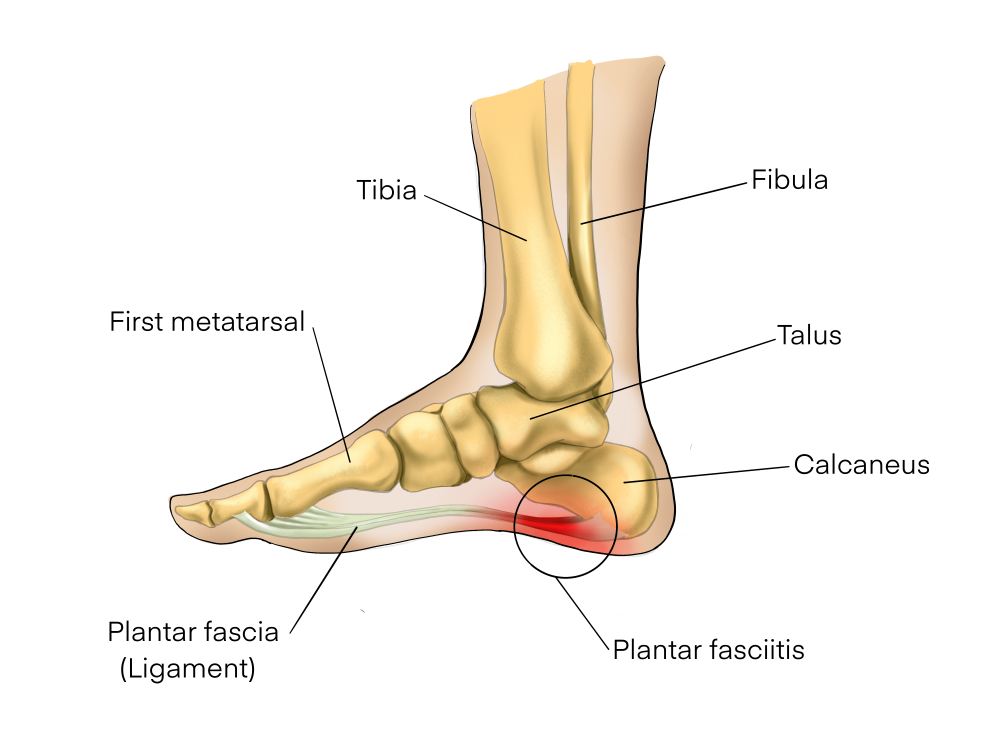

Painful Plantar Fasciitis Ligament Feet Disorder . Study Education